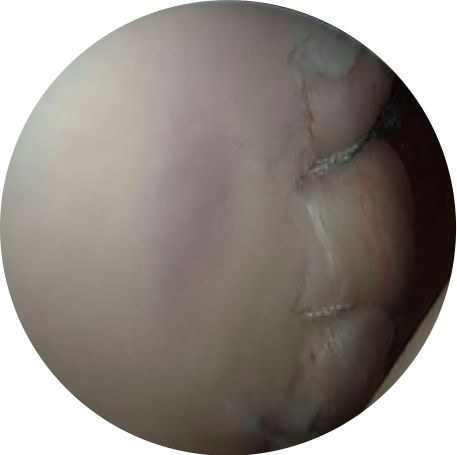

The labral tear after arthroscopic repair.

This video reviews an anterior-inferior labral tear with dislocation and arthroscopic repair.